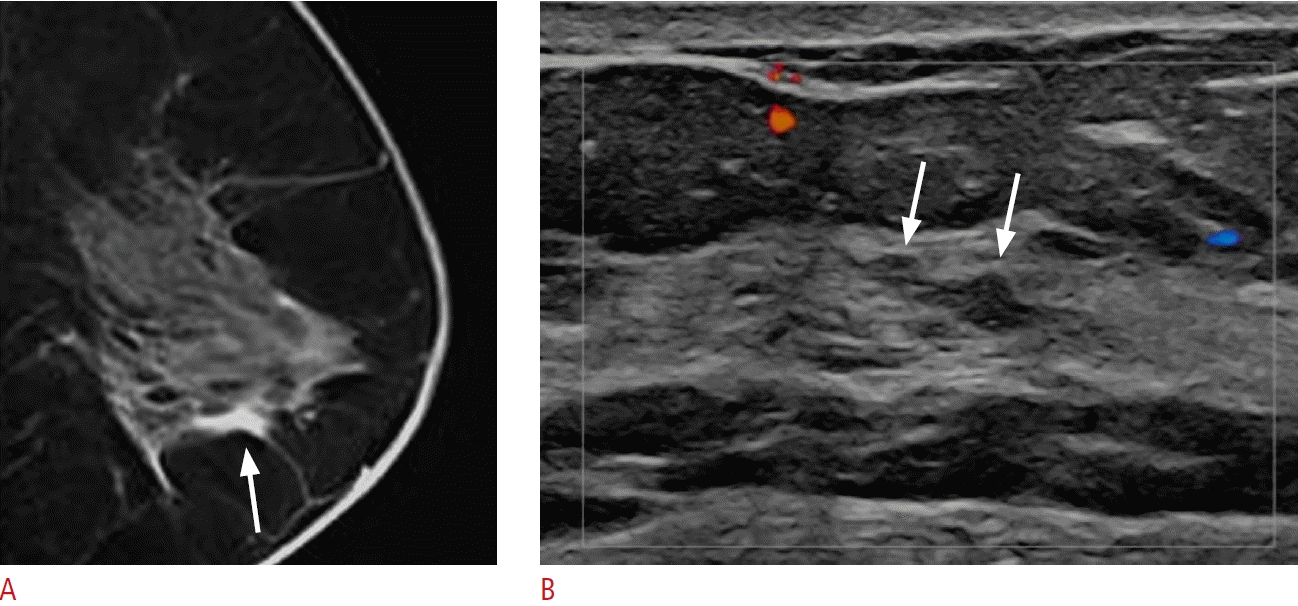

32. Okuno T, Watanabe T, Yamaguchi T, Konno S, Takaki R, Watanabe R, et al. Usefulness of color Doppler and strain elastography adjunctive to B-mode ultrasonography in the diagnosis of nonmass abnormalities of the breast: results of the BC-07 multicenter study of 385 cases. J Med Ultrason (2001). 2025; 52:157–168.